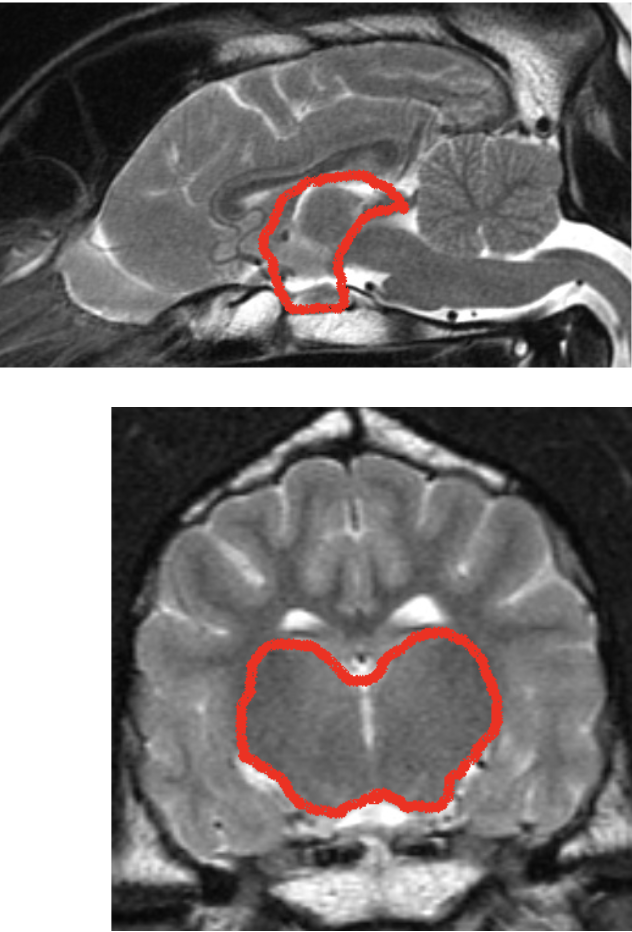

what structures are shown

corpus callosum (left)

internal capsule (right)

what structure is shown here

corpus callosum

what structures are shown here

internal capsule

corona radiata